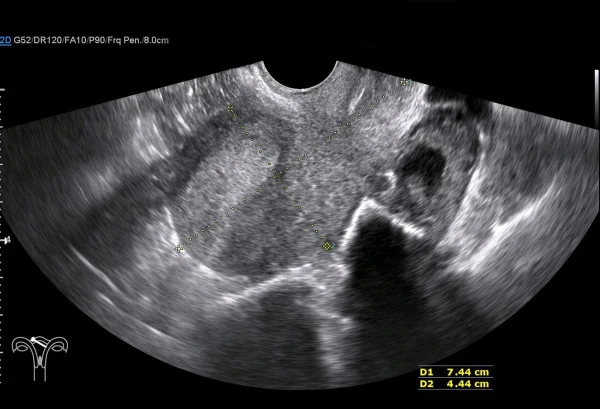

O diagnóstico das malformações uterinas

O diagnóstico das malformações uterinas é feito a partir da combinação de exames de imagem que permitem avaliar a forma e a estrutura do útero. Entre os principais métodos utilizados estão a ultrassonografia transvaginal, a histeroscopia, a ressonância magnética e a histerossalpingografia.